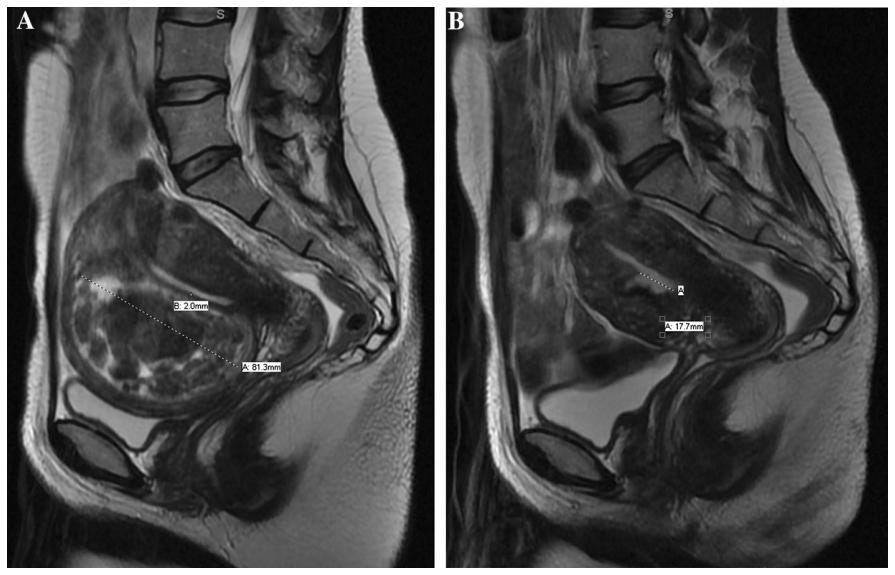

这种变化机制容易导致介入栓塞术后出现慢性持续阴道分泌物。另外术后变化可能潜在对子宫内膜影响,继而可能对生育产生负面影响。这种情况下,对于希望怀孕的患友,妇科手术可能对生育影响会较小些,尤其是粘膜下型肌瘤可以通过宫腔镜手术切取,临床疗效确切。文献报道显示肌壁间肌瘤边缘距离子宫内膜<2.4mm,或者肌壁间肌瘤最大径>5.1cm,术后肌瘤容易移位至粘膜下或者脱落排出。因此术前需告知患友,注意术后可能出现肌瘤脱落、排出风险,及时复诊。

子宫腺肌病合并粘膜下肌瘤介入栓塞术后变化对比